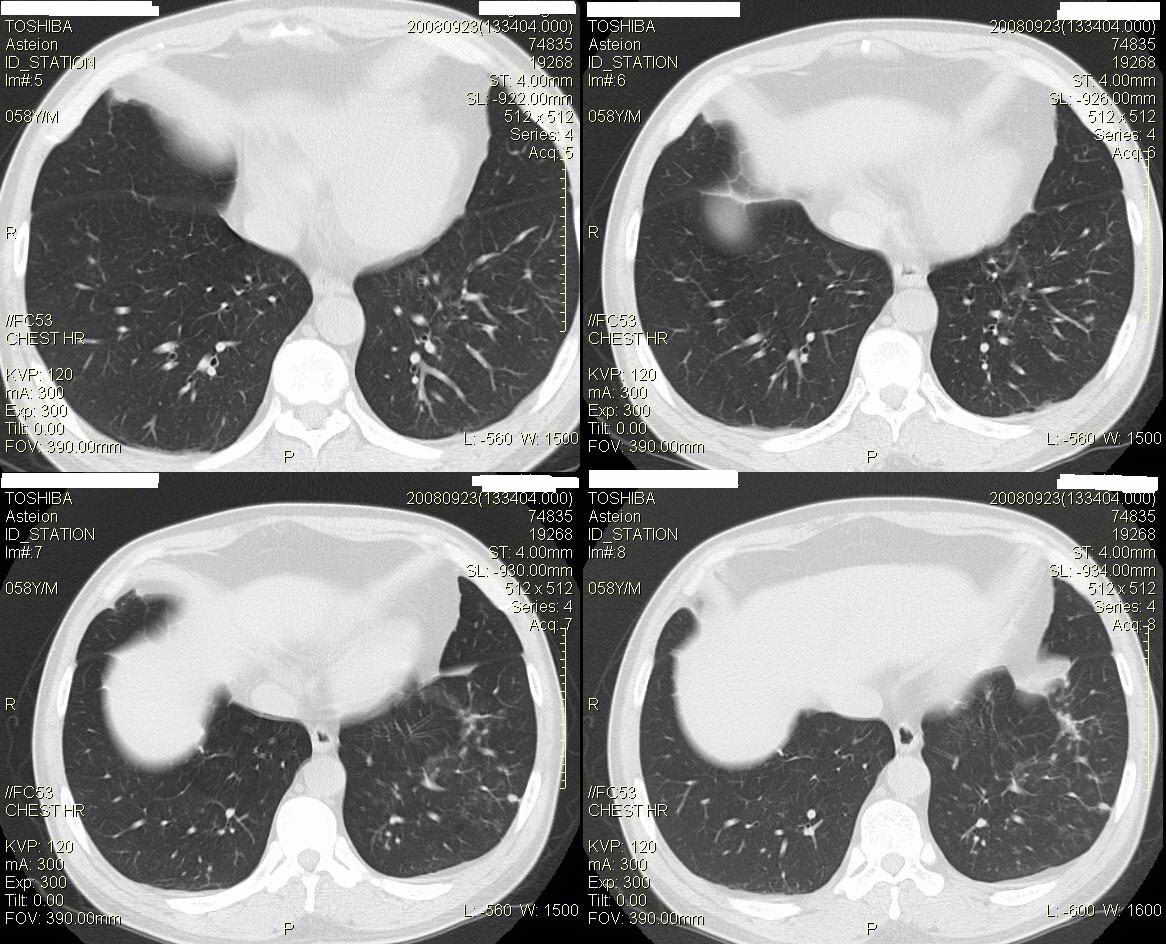

标题: CT15857:男性 58岁 咳痰带血 无发热 请各位大侠发表一下意见 [打印本页]

标题: CT15857:男性 58岁 咳痰带血 无发热 请各位大侠发表一下意见

两肺下叶肺纹理增多、增粗并呈“树芽状”改变。支气管扩张呈囊状,部分呈柱状改变。其周围可见散在的斑片样及条索样密度增高影,右肺下叶近叶间胸膜可见一形态不规则的高密度结节影,并与胸膜粘连。

考虑:支扩并发感染。

双肺多发炎性病灶,结核可能性大,建议抗炎治疗复查.右肺下叶前基底段结节灶,高度警惕肺癌可能

双肺间质性改变(间质纤维化?)伴支扩。右肺下叶有毛刺的小结节,考虑周围型肺癌可能性。